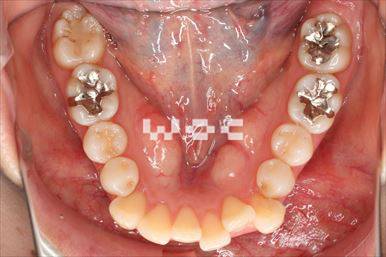

出っ歯舌側矯正

上下舌側矯正を希望。

通院状況や歯みがきの協力が良かったため、1年7ヶ月で治療を終えることができました。※装置と注意事項に関しては、大人の矯正装置一覧へ。

- 年齢:20歳女性

- 主訴:出っ歯が気になる

- 基本矯正料金:120万円

- 治療期間:1年7ヶ月

- 抜歯部位:上顎両側第一小臼歯